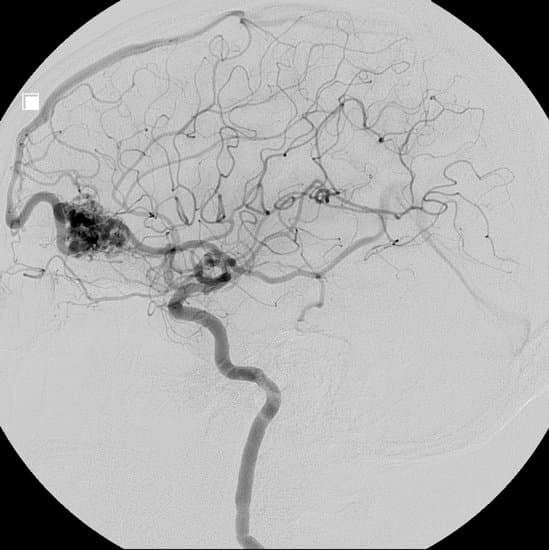

혈관 조영술: 혈관에 조영제를 주입하여 X선을 통해 혈관의 구조와 흐름을 시각화하는 검사로, AVM의 형태와 혈류를 정확하게 볼 수 있습니다.